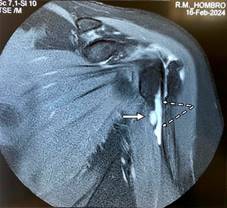

Se trata de paciente femenino de 69 con dolor en el hombro izquierdo de seis meses de evolución, principalmente con movimientos de abducción y flexión de codo. A la exploración de hombro izquierdo: arcos de movimiento limitados en abducción a 90o por dolor al igual que rotación externa de 45o, a la palpación masa dolorosa de aproximadamente 2 cm en borde interno del tendón de la porción larga del bíceps por debajo de la corredera bicipital. Prueba de choque de Neer, Hawkins y prueba de Yergason positivas; pruebas de inestabilidad de la articulación glenohumeral negativas. Las radiografías simples no mostraron hallazgos anormales. La resonancia magnética mostró: tendinosis del supraespinoso con ruptura parcial en su inserción, además de acromion tipo III con osteofitos subacromiales causantes de pinzamiento (Figura 1); en ponderación T2 se encontró tendinopatía de la porción larga del bíceps braquial con incremento de líquido en la corredera bicipital y quiste sinovial en su tercio proximal de 2.0 × 1.4 × 1.2 cm, con apariencia de estar encapsulada por la vaina del tendón bicipital (Figuras 2 y 3). Se canalizó a cirugía articular.

Figura 1: Imagen de resonancia magnética ponderada en T2, en corte coronal. Se muestra acromion tipo III, osteofitos subacromiales (flecha) y tendinosis y ruptura parcial del tendón supraespinoso a nivel de su inserción (flecha punteada).